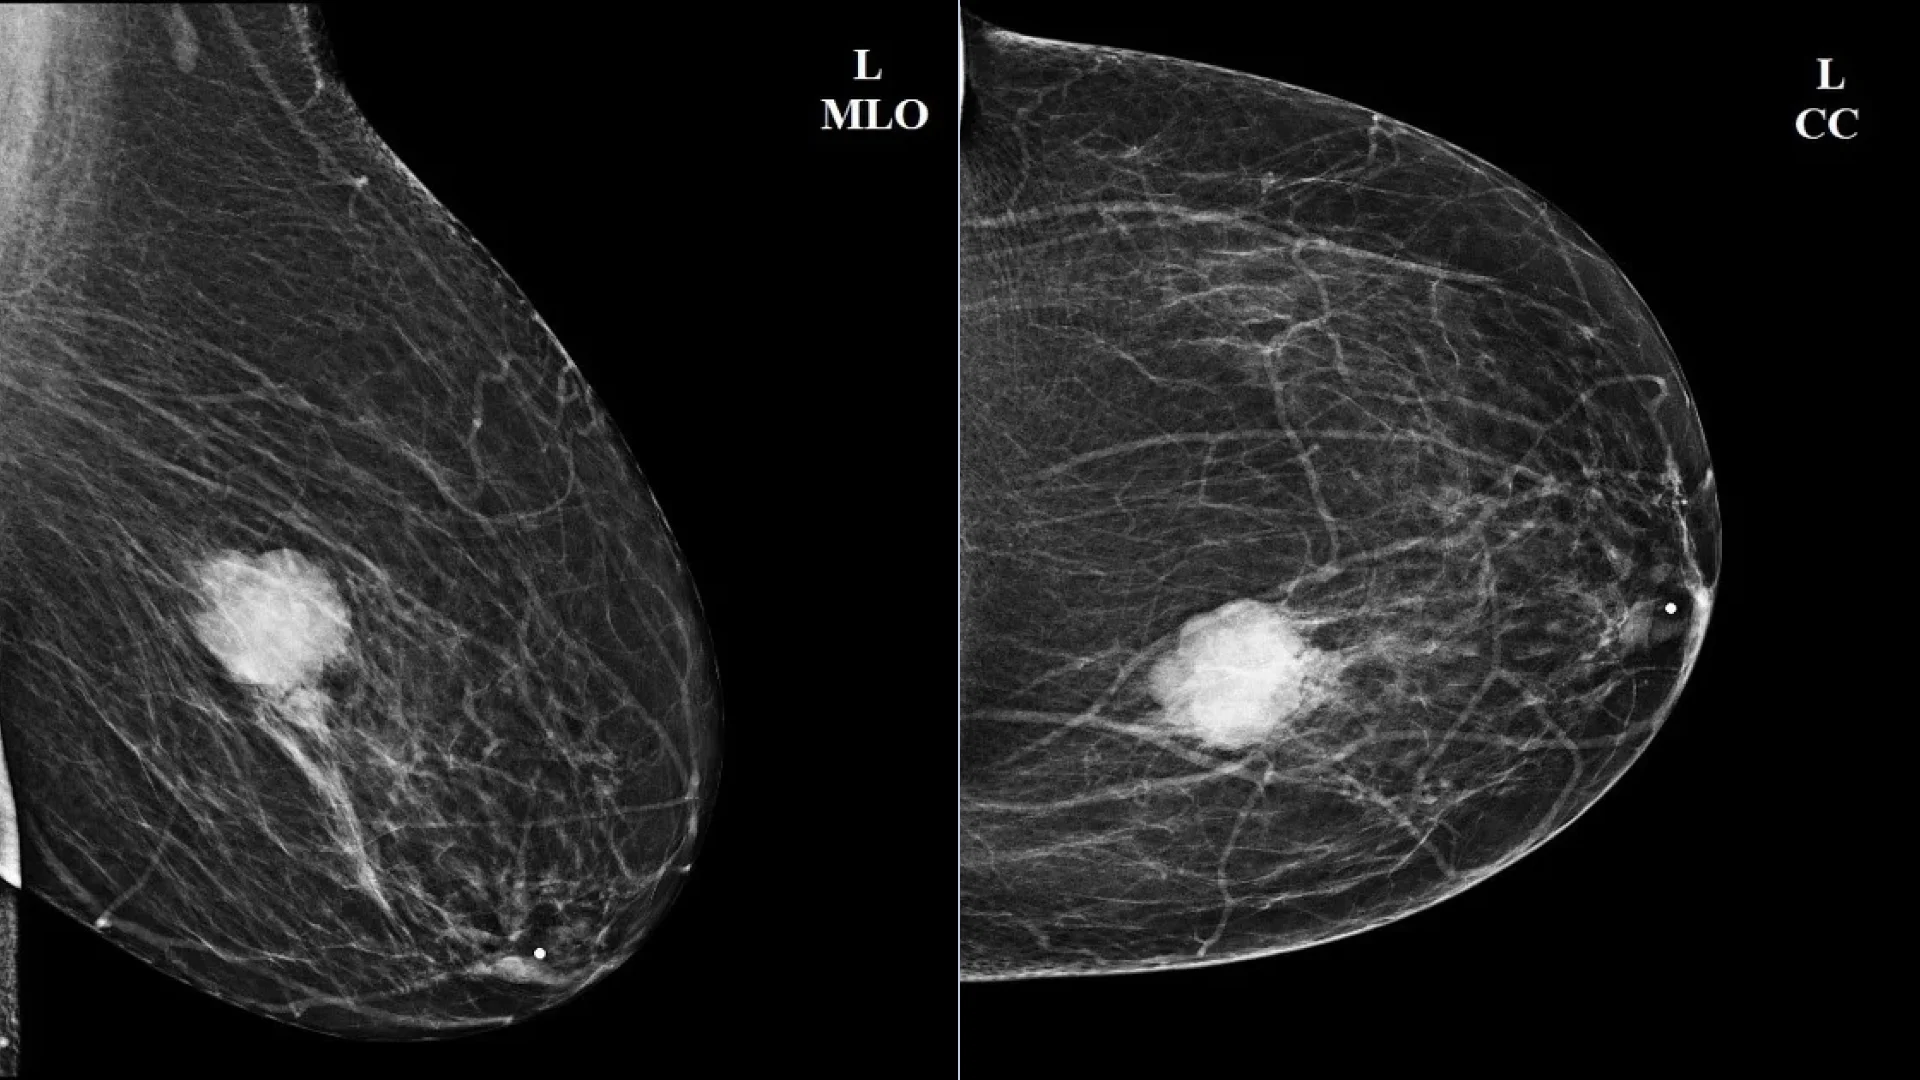

Mammography of the left breast in two projections: intraductal papilloma

Mammography of the left breast in two projections: intraductal papilloma. Author: Ammar Ashraf. Source: Radiopaedia [11]